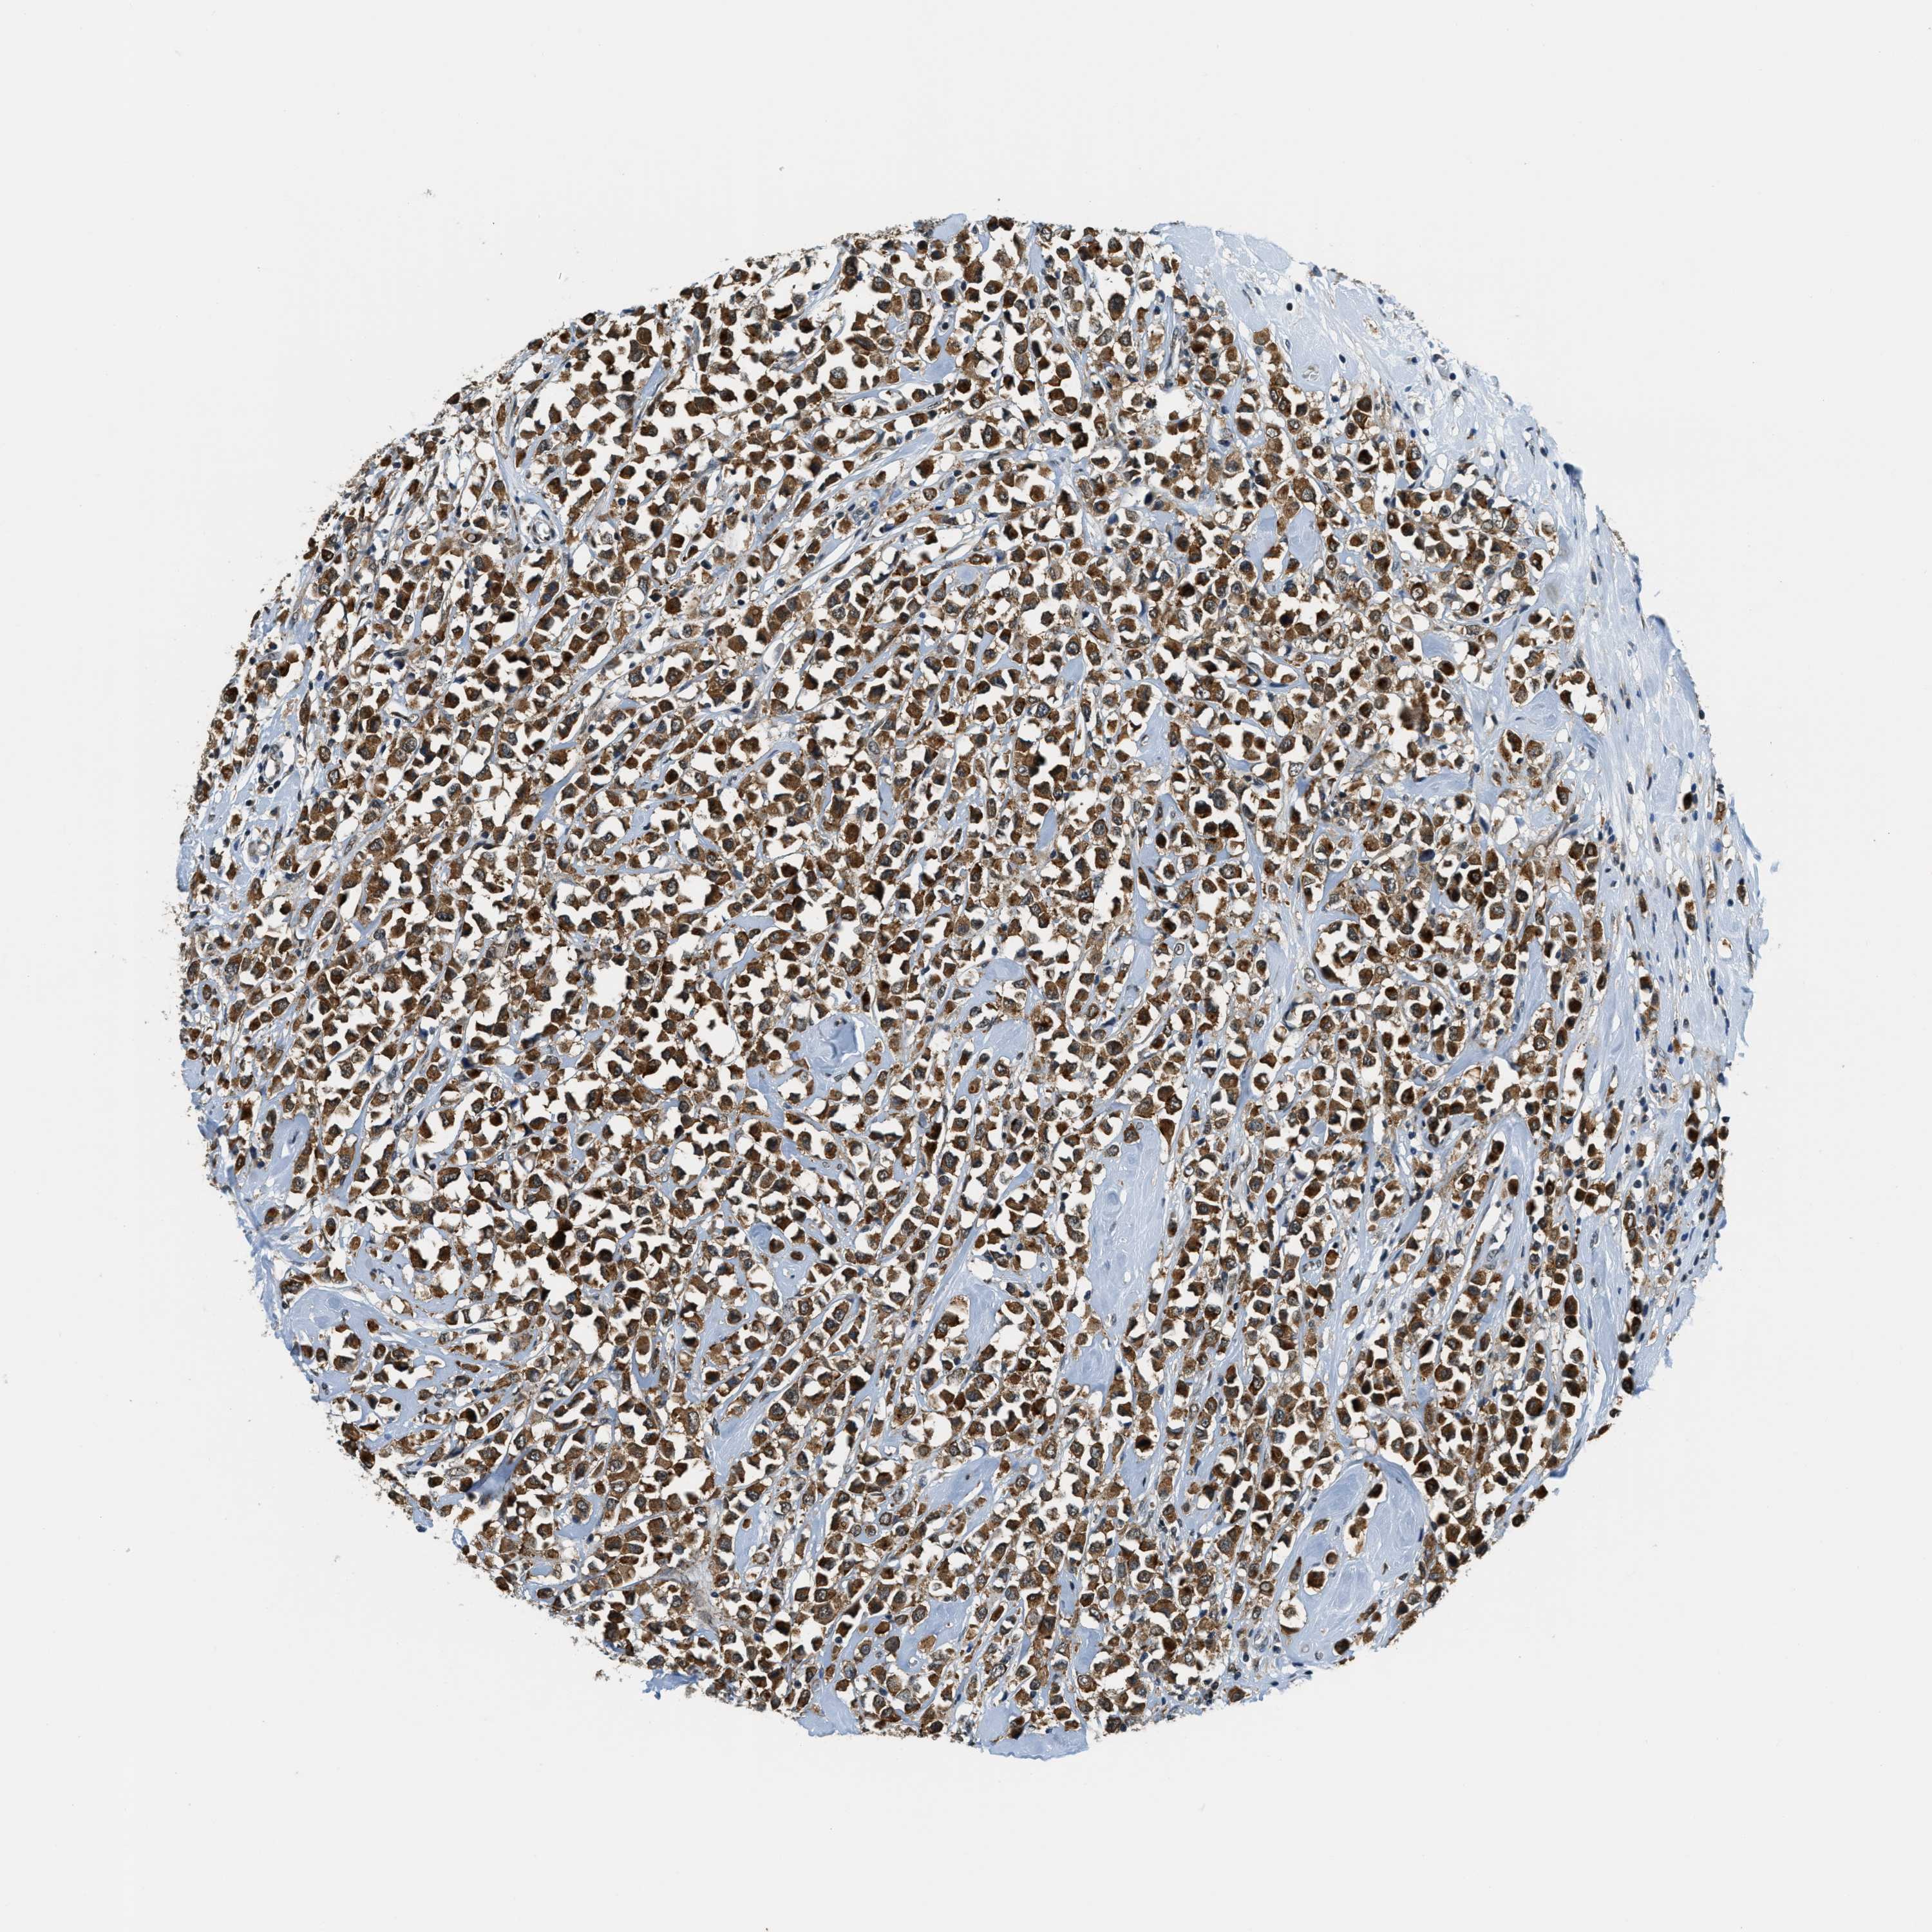

CANCER BREAST CANCER Show tissue menu

Breast cancer

Human cancer